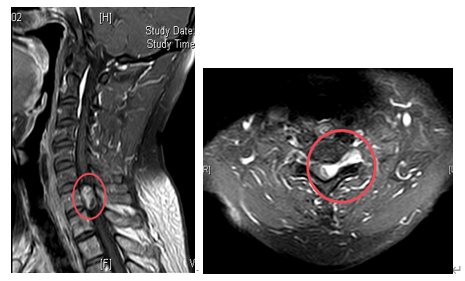

术前核磁检查颈胸段椎管内存在占位性病变,且脊髓已被挤压成线形。

若不尽快手术切除肿瘤,随着肿瘤持续增大,脊髓受压程度会不断加重,进而造成不可逆的神经损伤,最终甚至可能导致四肢瘫痪。接下来,脊柱外科一区主任、主任医师许宇霞带领团队成功为张淮实施了高难度颈胸段椎管内肿瘤切除术。术中快速病检提示肿块为“神经鞘瘤”,这类肿瘤多为良性肿瘤,手术切除后预后良好,复发率低。术后张淮恢复良好,原有颈肩疼痛消失,左上肢麻木无力及右下肢行走无力等症状均显著改善。

术后复查核磁检查,颈胸段椎管内肿瘤已切除干净。